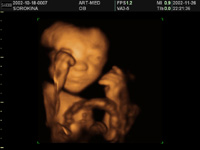

3D/4D УЗИ – «четвертое» измерение!

Сегодня мечты стали реальностью. С появлением 3-D и 4-D УЗИ будущие родители могут не только убедиться в том, что с малышом все в порядке, но и увидеть, как он будет выглядеть, когда появится на свет.

3D-УЗИ иногда называют четырёхмерным. Четвёртым измерением, в данном случае, является время. То есть трёхмерное изображение в реальном времени называется четырёхмерным. Данное слово придумано разработчиками приборов. Таким образом, используемыми видами трехмерного УЗИ являются 3D (static – объемное статичное изображение), 4D (real time – объемное изображение плода в движении в реальном режиме времени) и STIC (исследование сердца плода в трехмерном режиме). Объемные изображения позволяют лучше рассмотреть некоторые структуры, труднодоступные для исследования в обычном двумерном режиме, облегчают понимание изображения как будущим родителям, так и врачам других специальностей.

Дополнительная информация, которую дает трехмерное УЗИ, особенно ценна для диагностики внешних пороков развития. После 3D-УЗИ можно развеять все свои сомнения, лично пересчитав пальчики на маленьких ручках и ножках и убедившись в отсутствии других внешних пороков. Кстати, подозрение на наличие таких пороков можно считать медицинским показанием для проведения трёхмерного исследования. Благодаря 3D-УЗИ врачи могут оценить различные части тела плода в трёх проекциях одновременно, что очень важно для выявления аномалий внутриутробного развития плода. Данные трёхмерного исследования дают дополнительную информацию для диагностики пороков развития: конечностей, лица, позвоночного столба.

То, какую информацию мы получаем и как выглядит трехмерная картинка, зависит от срока беременности, на котором проводится обследование. Получить объемное изображение при помощи трехмерного УЗИ можно уже тогда, когда крошка в длину всего 15 мм. К 8 неделе беременности можно различить головку и туловище, формирующиеся конечности. С 10 по 16 недели можно увидеть кроху целиком – его позу, ручки, ножки, пуповину – но без мелких деталей. Иногда на этих сроках удаётся, пусть и недостаточно четко, рассмотреть личико маленького человечка.

Наиболее оптимальные сроки для трехмерного УЗИ – от 12 до 32 недель беременности.

На таких сроках будущие родители смогут увидеть даже живую мимику своего малыша, а приблизительно на 18-21 неделе беременности можно различить пол будущего ребенка. Таким образом, с помощью трехмерного УЗИ будущая мама может увидеть изображение своего малыша, близкое к фотографии, и получить видеозапись его движений в реальном времени.